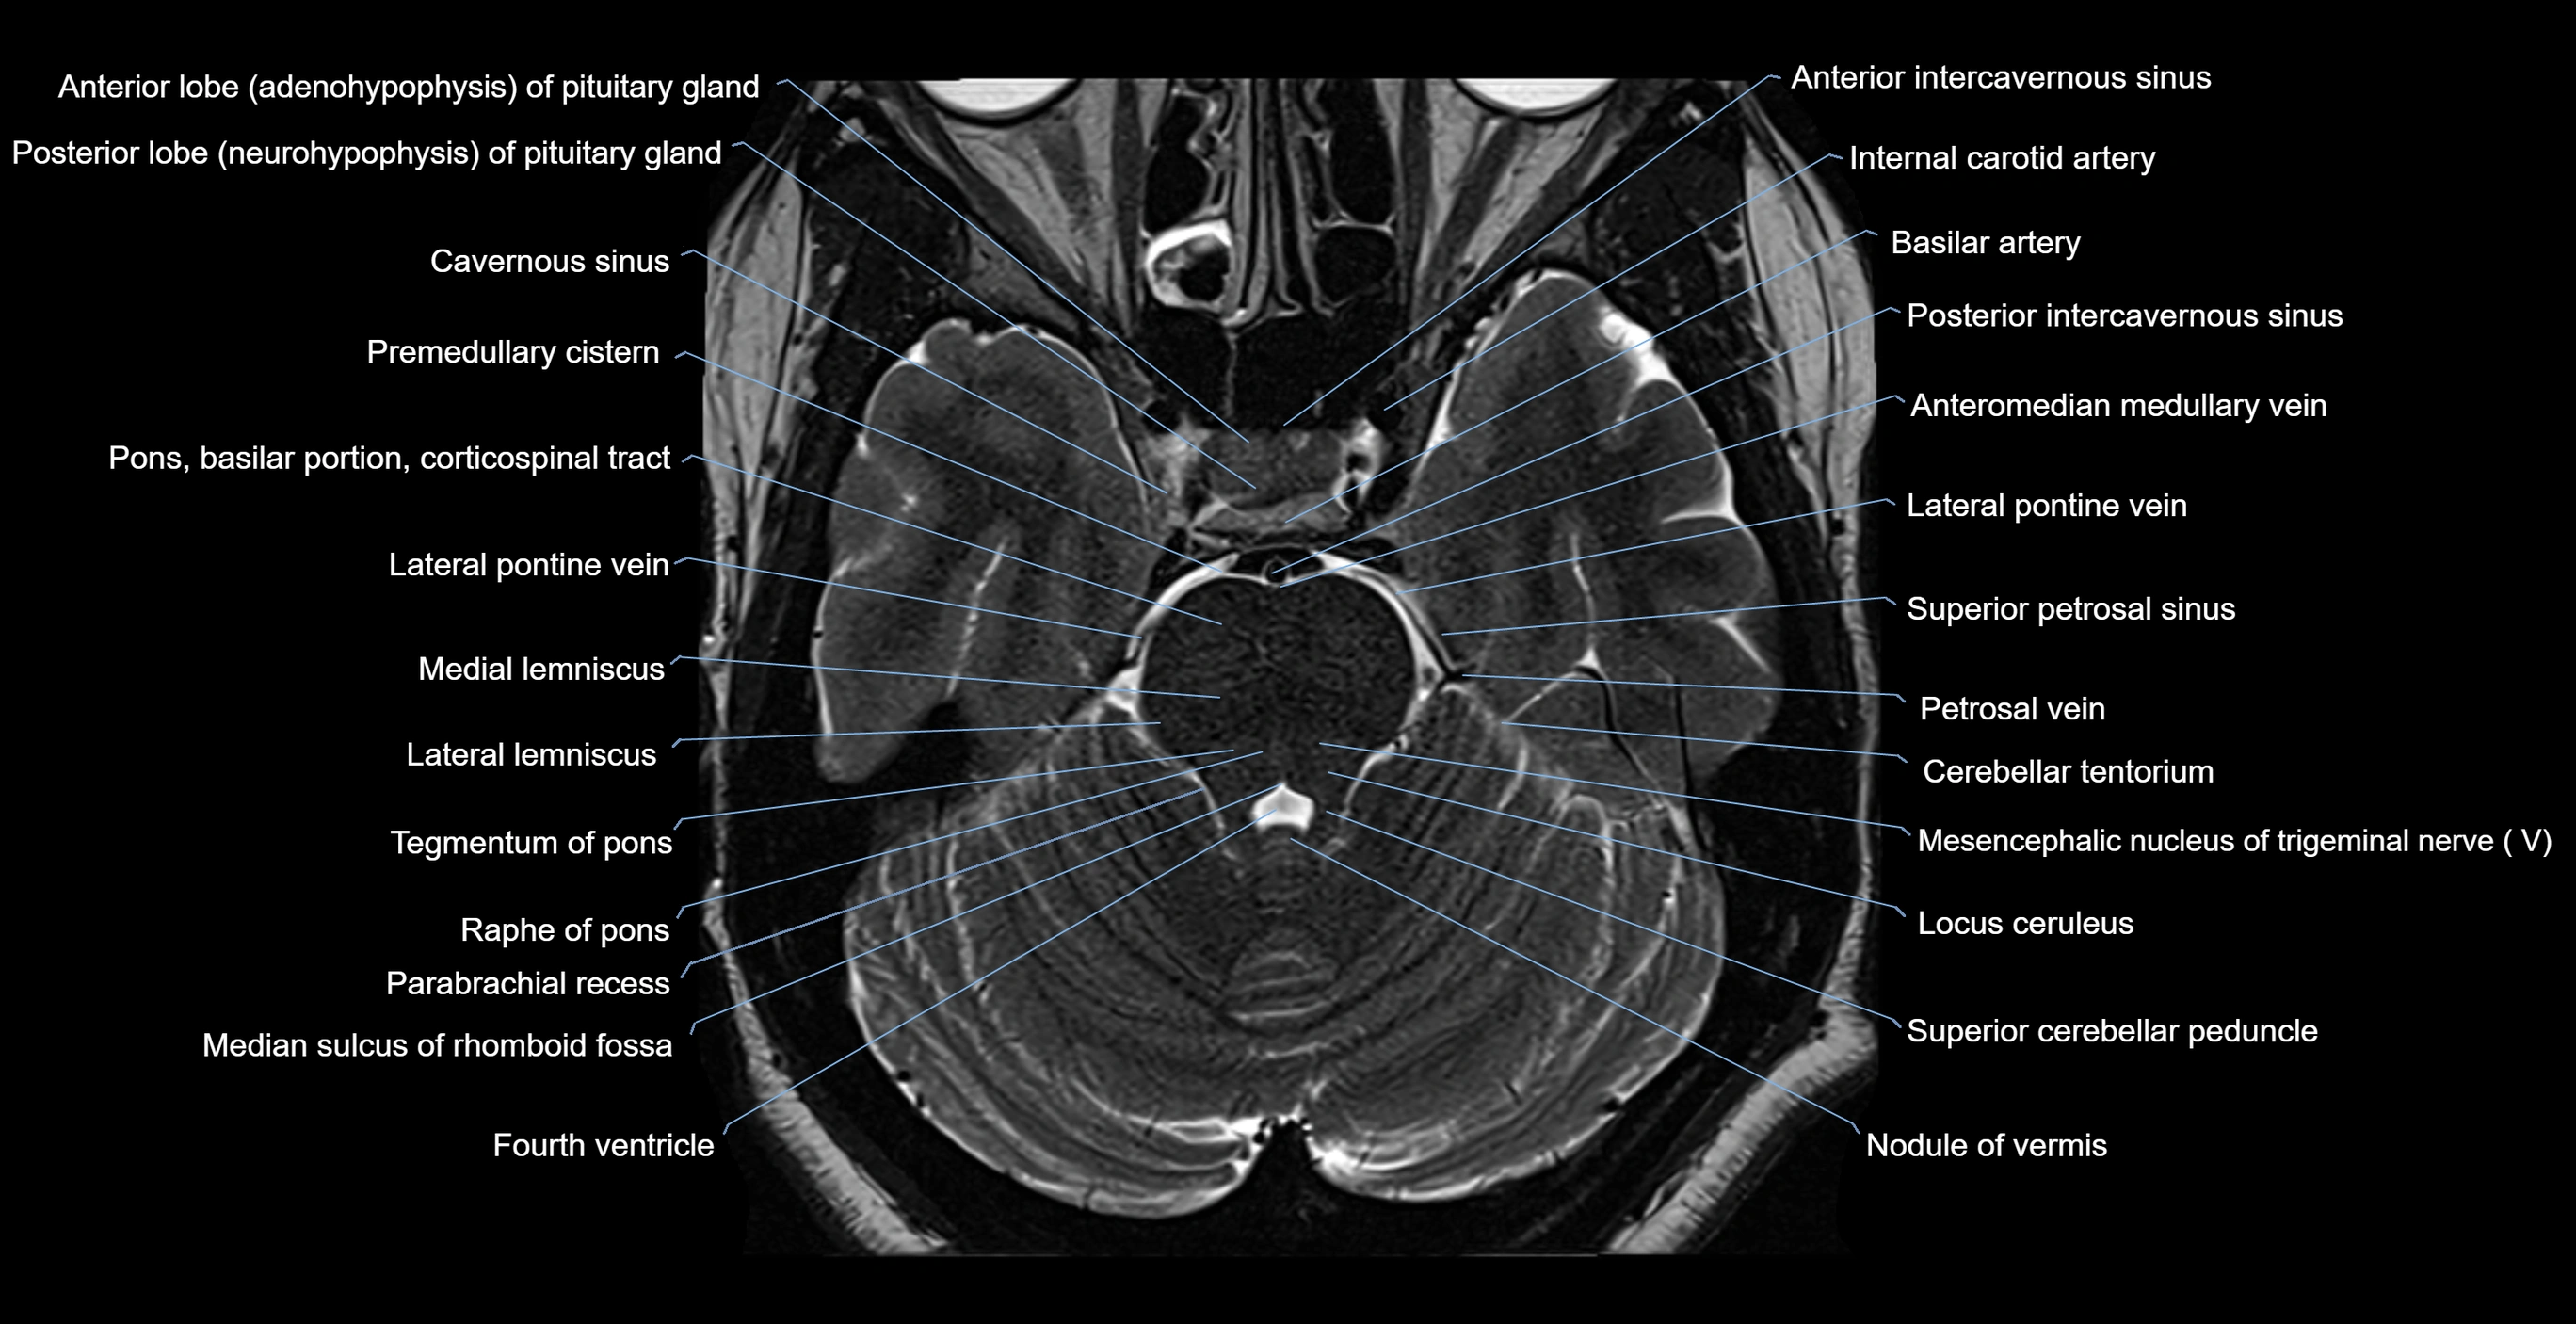

- Anterior intercavernous sinus

- Lateral pontine vein

- Locus ceruleus

- Median sulcus of rhomboid fossa

- Nodule of vermis

- Parabrachial recess

- Posterior intercavernous sinus

- Raphe of pons

- Superior cerebellar peduncle